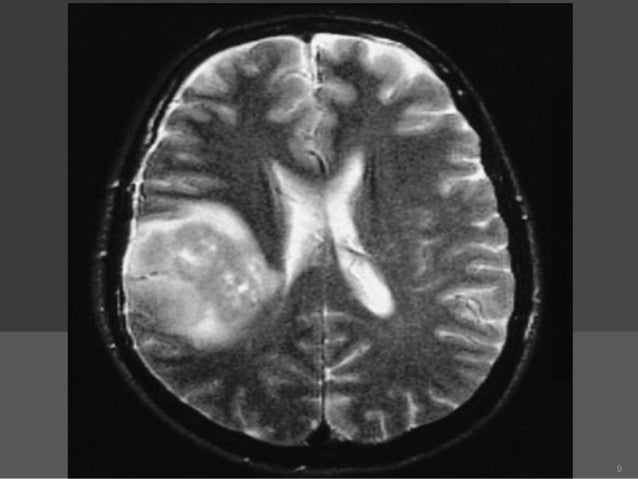

It is used to diagnose tumors, infection, inflammation, and other brain disorders. A biopsy means taking a small tissue sample from your brain and examining it under the microscope. A brain tumor is an abnormal growth of tissue in the brain or central spine that can disrupt proper a biopsy may be necessary, so a pathologist can be brought in to help identify the brain tumor type.

Specimens are taken from normal tissue, edema, solid tumor and central necrosis.

A stereotactic biopsy is a surgical procedure where a thin needle is inserted into the brain by a neurosurgeon to extract a small piece of tissue to examine. A biopsy is a major procedure, and it is the most definitive test for brain tumor diagnosis. A brain biopsy can help doctors diagnose brain illnesses, allowing them to devise treatment plans. These are generally seen in stereotactic biopsy: